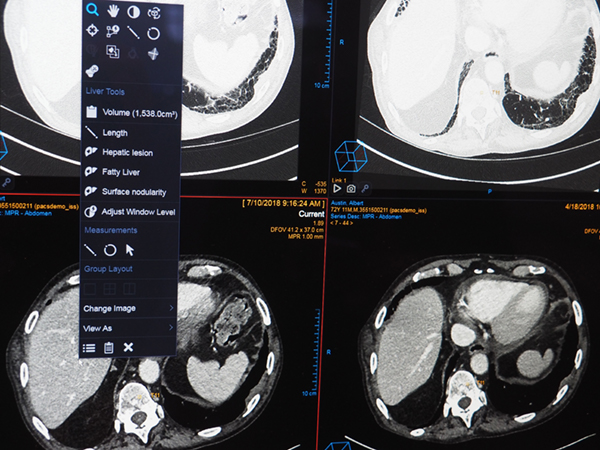

診断補助(Diagnostic Aide)として,腹部領域でCTのアキシャル画像から臓器のセグメンテーションと自動認識を行う。肝臓や腎臓といった臓器を自動で判別し,その臓器に合った測定ツールを提示する。腹部の病変の自動抽出と計測を行い,計測結果は自動でレポートシステム(Vue Reporting)に反映される。レポートのテキストはハイパーリンクとなっており,ビューワの病変部とのリンクがつけられるほか,計測データはダイナミックに変化する。

Diagnostic Aide(W.I.P.)。臓器のセグメンテーションと自動認識を行い測定ツールを表示。

Diagnostic Aide(W.I.P.)。計測結果は自動でレポートに反映。数値はインタラクティブに変化する。